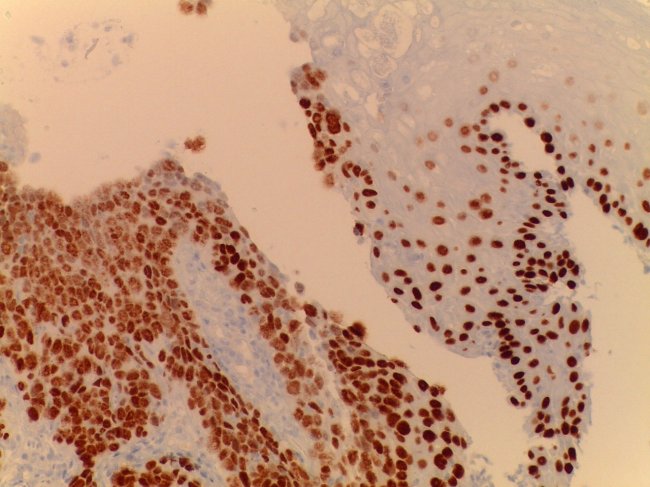

Quando a suspeita persiste torna-se necessário recorrer à biopsia para completo esclarecimento da situação. Só depois do anatomopatologista observar a colheita de tecido ao microscópio é que pode confirmar a presença de células cancerígenas.